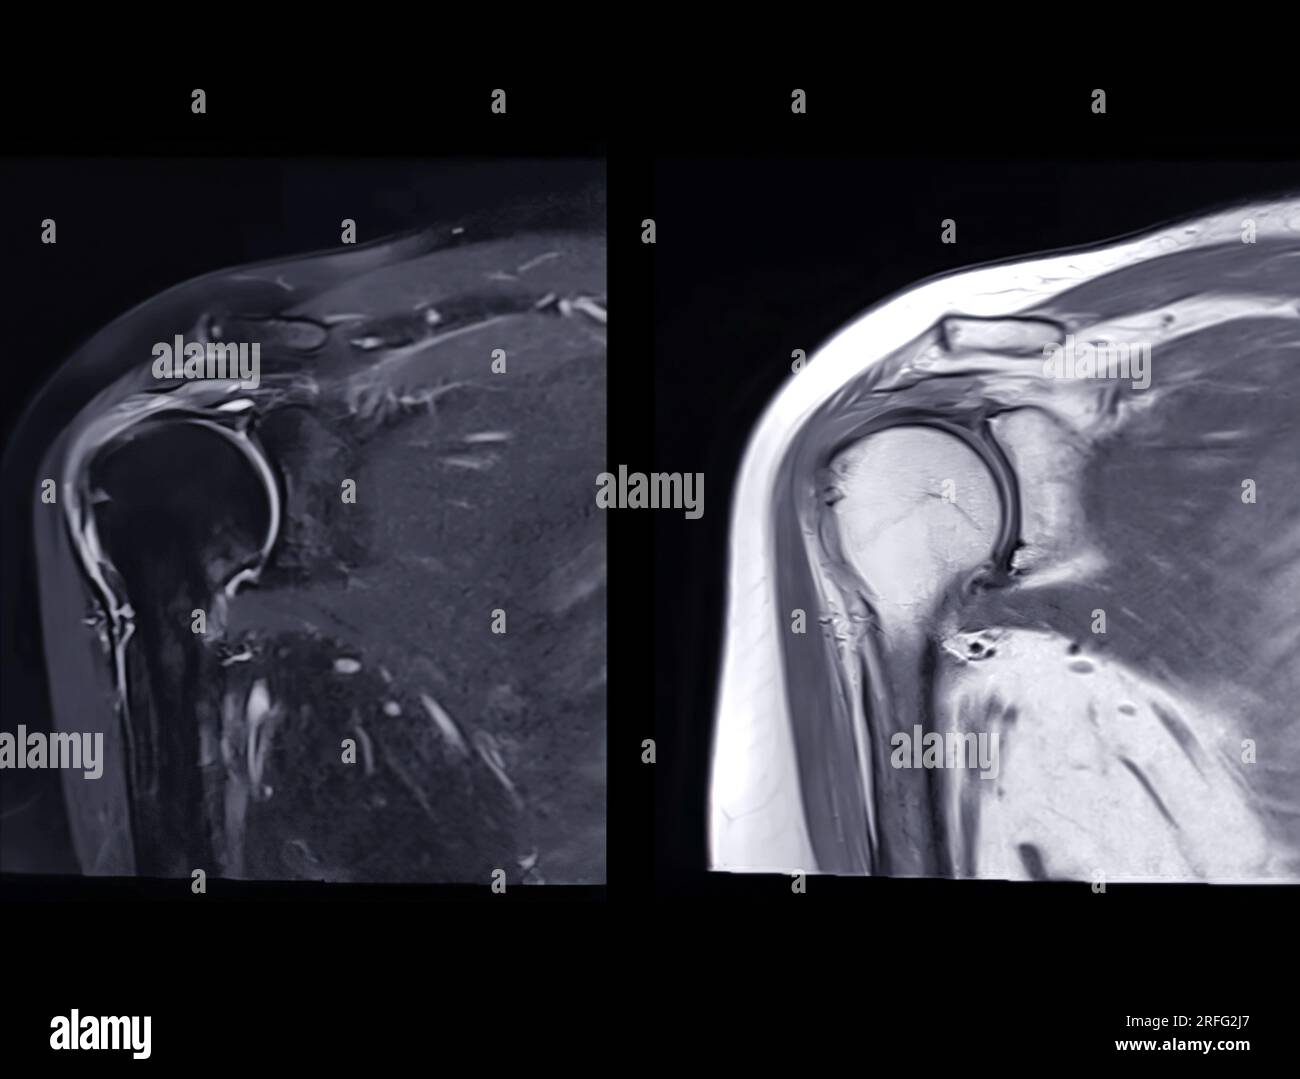

Resonance Imaging or MRI of Shoulder Joint Coronal T2 FS and PDW for diagnostic What Can Mri Of Shoulder Detect magnetic resonance imaging (mri) of the shoulder is done to: magnetic resonance imaging (mri) of the shoulder uses a powerful magnetic field, radio waves and a computer to produce. The mri allows accurate assessment of. a shoulder mri is a test that uses a magnetic field to take pictures of your shoulder. A shoulder mri can diagnose. What Can Mri Of Shoulder Detect.

Normal shoulder MRI How to read a shoulder MRI Kenhub What Can Mri Of Shoulder Detect A shoulder mri can diagnose tears of the rotator cuff, labrum, and tendons. what can a shoulder mri diagnose? magnetic resonance imaging (mri) of the shoulder uses a powerful magnetic field, radio waves and a computer to produce. Learn more about what it’s for,. The mri allows accurate assessment of. in particular, the images include your muscles,. What Can Mri Of Shoulder Detect.

Normal shoulder MRI How to read a shoulder MRI Kenhub What Can Mri Of Shoulder Detect magnetic resonance imaging, or mri, uses a magnet to examine the inside of your body, useful for diagnosing shoulder pain and. the evaluation of the shoulder, and especially its soft tissue structures, is best done with an mri. a shoulder mri is a test that uses a magnetic field to take pictures of your shoulder. Learn more. What Can Mri Of Shoulder Detect.